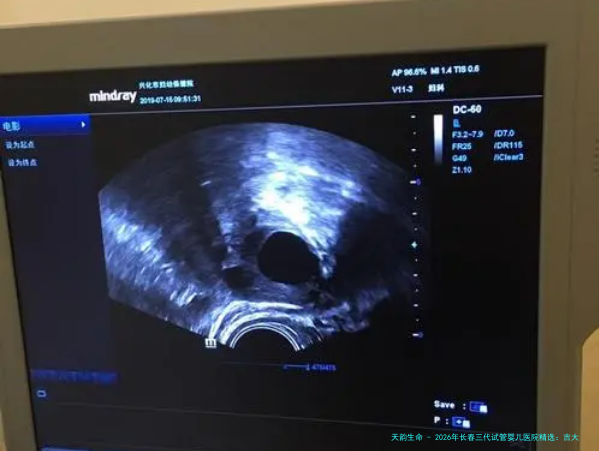

| 长春市妇产医院生殖医学中心 | 公立专科三甲 | 医院1896年成立,生殖中心2011年获批 | 百年老院,妇幼专科优势明显。生殖中心与产科、妇科无缝衔接,为患者提供孕前-孕中-产后一体化管理。 | 对于女性不孕因素的诊疗经验极为丰富。在多囊卵巢综合征、子宫内膜异位症等导致的不孕方面,有系统的诊疗体系。 | “因为是妇产专科医院,做各种检查和保胎都特别方便,不用来回跑。主任非常负责,每次B超都亲自做,看得特别仔细。” |